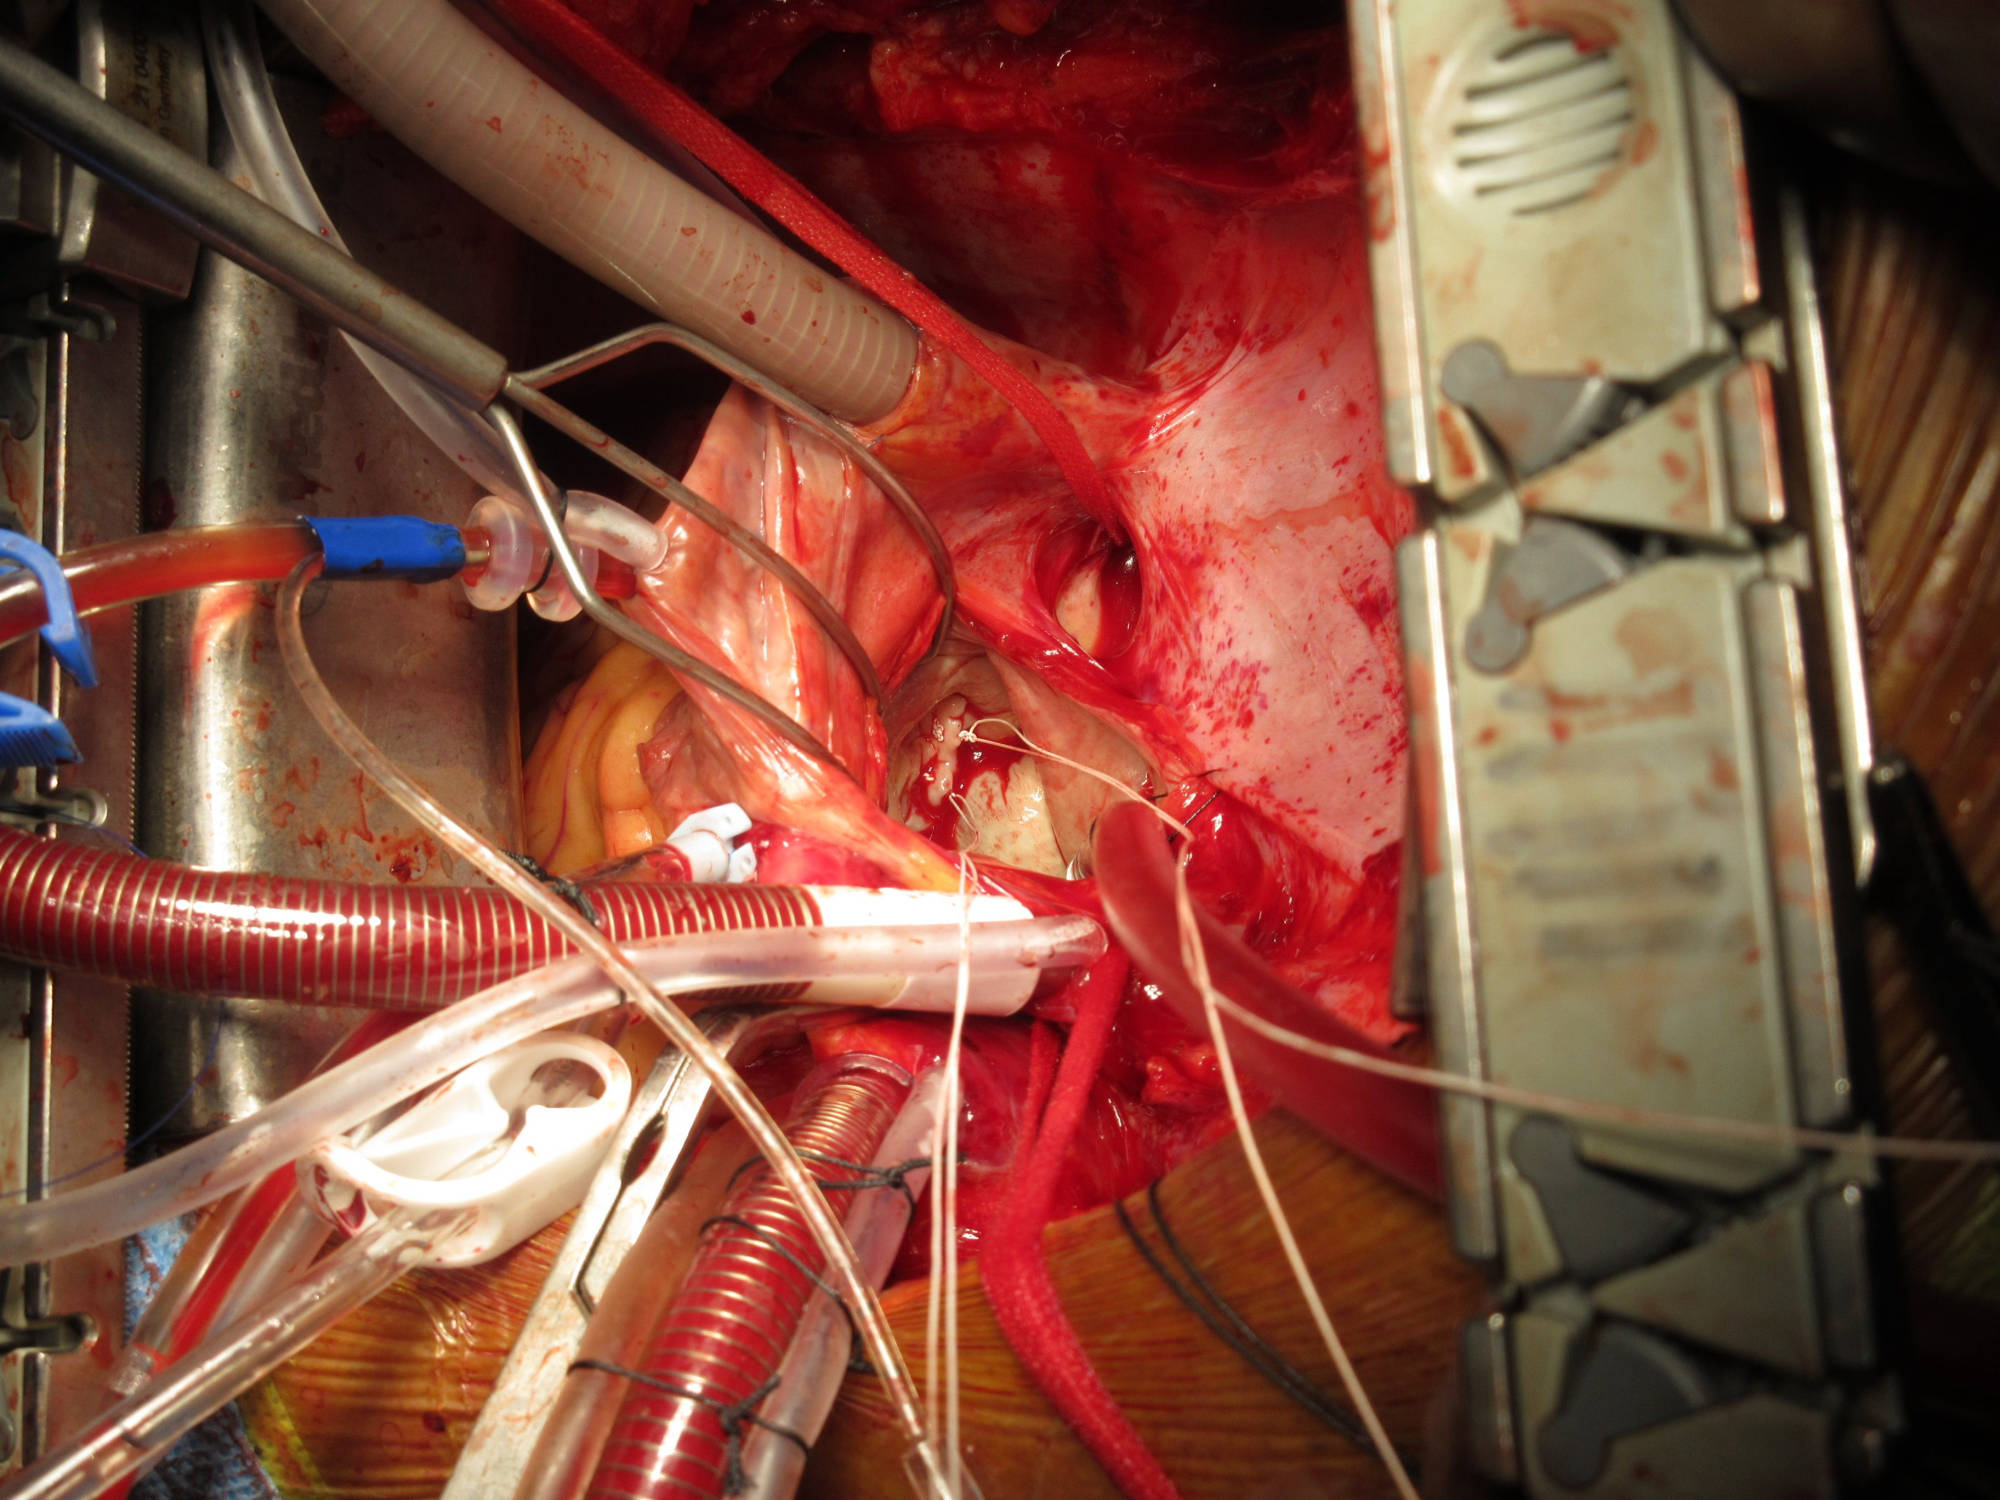

Aortic Dissection + CABG

A 58 year old patient who had renal transplant 25 years earlier developed Aortic Dissection and Coronary Artery disease. He underwent successful Bentall's operation (replacement of aortic valve and ascending aorta and reimplantation of coronary arteries) with CABG (3 grafts). He did not require renal dialysis throughout his stay in the hospital and was discharged with normal renal function.